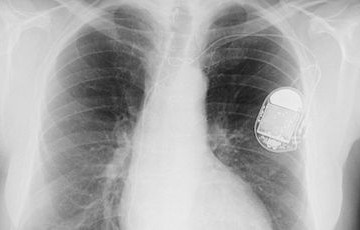

Providing evaluation and ongoing follow-up for patients with implanted pacemakers and defibrillators.